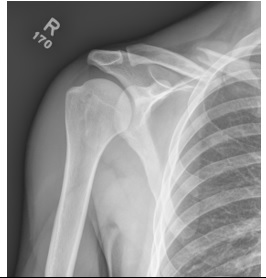

Seorang laki-laki, 38 tahun, diantar ke IGD RS dengan keluhan nyeri bahu kanan setelah melakukan overhead smash saat bermain bulu tangkis sejak 1 jam yang lalu. Tiga tahun lalu pasien pernah mengalami cedera bahu kanan dan diterapi di IGD pula. Pada pemeriksaan fisik didapatkan ROM aktif dan pasif bahu kanan terbatas. Pasien tampak memegangi lengan bawah kanan dengan tangan kirinya.

Apa diagnosis kerja yang paling tepat untuk pasien ini?

| Acromioclavicular joint disruption dextra | |

| Dislokasi anterior articulatio glenohumerale dextra | |

| Dislokasi posterior articulatio glenohumeral dextra | |

| Fraktur tertutup clavicula dextra | |

| Fraktur tertutup humerus proksimal dextra |